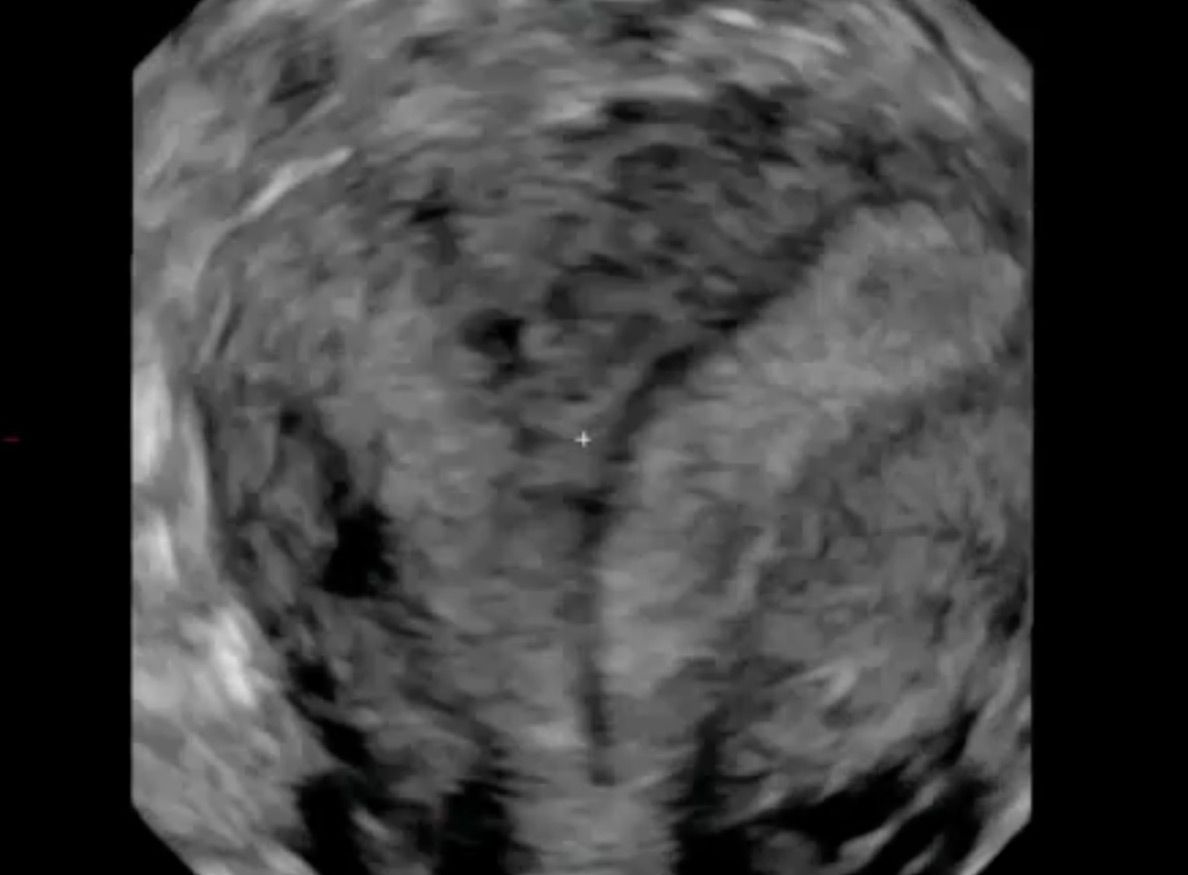

Adenomyosis

Die Endometriose ist eine Erkrankung, die durch Auftreten von Gebärmutterschleimhaut-ähnlichem Gewebe außerhalb der Gebärmutterhöhle  geprägt ist. Das abnorm lokalisierte Gewebe kann ein Vielfalt an Symptomen auslösen. Von zyklusabhängigen Schmerzen, Blutungsunregelmäßigkeiten bis hin zum unerfüllten Kinderwunsch können diese Probleme reichen.

Aufgrund der Vielfalt an möglichen Symptomen handelt es sich in der Differentialdiagnostik um ein Chamäleon. Insbesondere die Manifestation innerhalb des Eierstocks (Endometriome, Schokoladenzysten) oder innerhalb der Gebärmuttermuskulatur  weisen ein charakteristisches Ultraschallbild auf. Daher ist die Vaginalsonographie ein wichtiger Bestandteil der Diagnostik zur Erkennung der Endometriose.